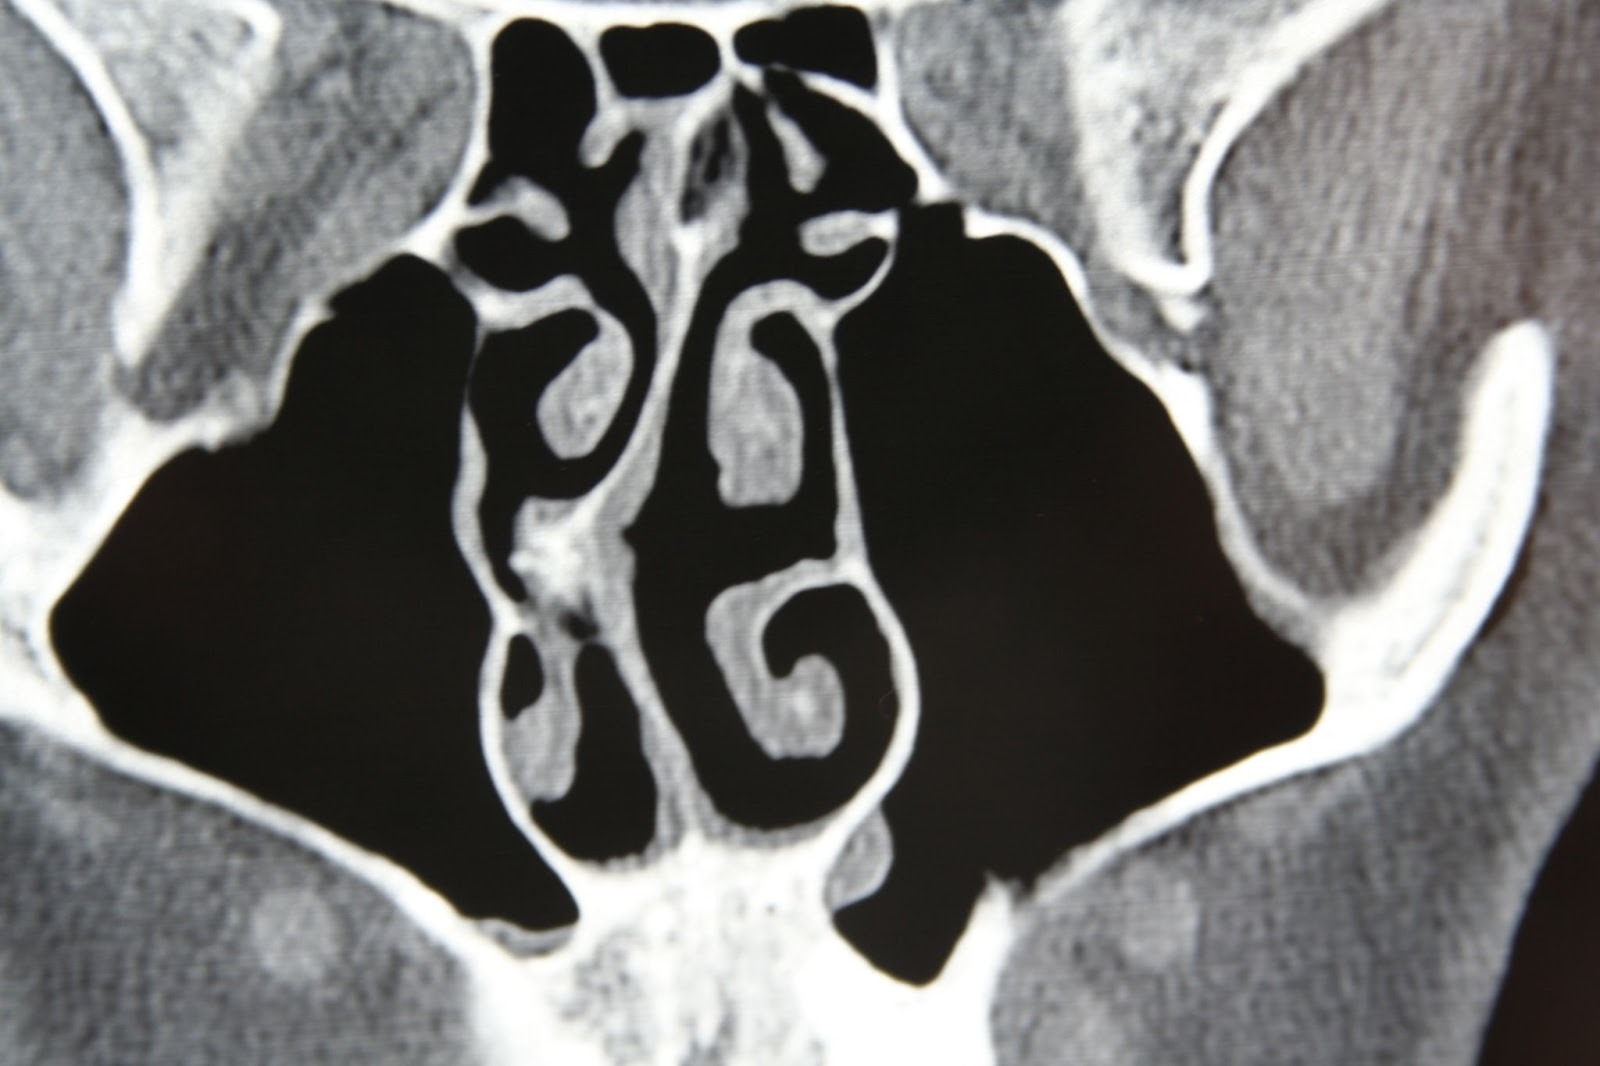

How a Deviated Septum Is Diagnosed

Diagnosis typically begins with a physical exam by a healthcare provider or ENT specialist. Evaluation may include:

- Visual inspection of the nasal passages

- Use of a nasal speculum or endoscope

- Discussion of symptom patterns and duration

Imaging studies, such as a CT scan, may be recommended if chronic sinus issues or surgical planning are involved. Diagnosis focuses not just on anatomy, but on whether the deviation explains the patient’s symptoms.